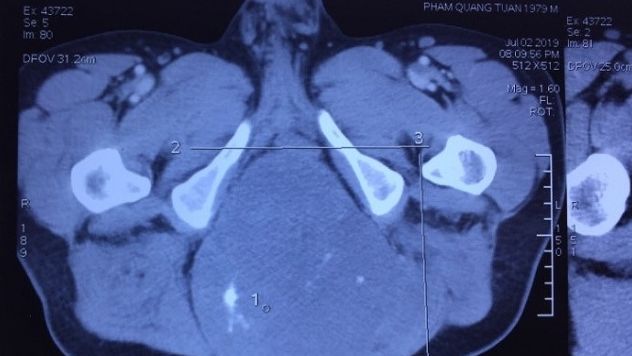

Loại bỏ khối u nguyên sống khổng lồ vùng cùng cụt

Khối u khoảng 20 cm ở vùng cùng cụt của bệnh nhân. Mới đây, Bệnh viện Trung ương Quân đội 108 tiếp nhận anh Phạm Quang T (40 tuổi, Hà Nội...